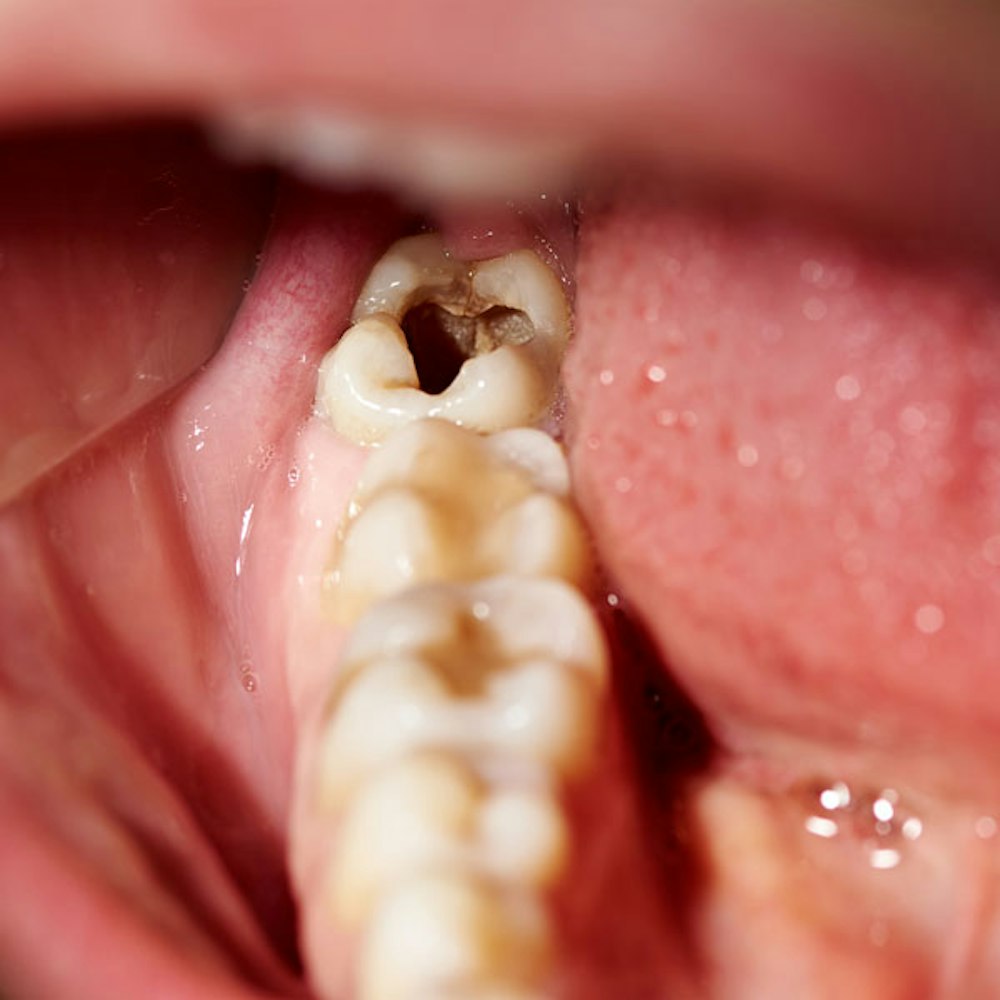

- Relieve Pain: Severely damaged and decaying teeth can cause daily tooth pain. Tooth extractions can give you the freedom to live comfortably and eliminate discomfort.

Take a Closer Look at Tooth Extraction